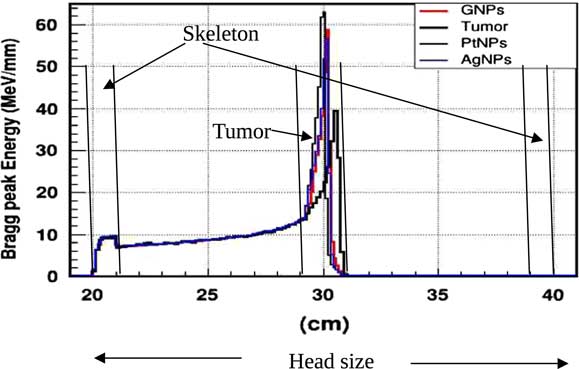

In practice, proton therapy can be used in two ways known as passive scattering and pencil beam. The first technique is based on a single scattering foil (made out of lead) used to broaden the beam. In the second technique, the proton beam is deflected with a magnetic field to generate a narrow monoenergetic pencil beam and scan it magnetically across the tumour. Both of these techniques should be used carefully. Our principal goal is to investigate on how NMs affect on proton therapy. The deposited energy along the head is plotted in the Figure 4. This plot is obtained from a Monte Carlo simulation of 106 protons beam energy of 125 MeV. This figure shows that NMs enhance in a significant way the deposited energy in the tumour. Furthermore, the platinum NPs (PtNPs) present the more efficiency. In order to investigate deeply the enhancing proton therapy by NMs in tumour, we have plotted the deposited energy only along the tumour ranging between 29·2 and 30·8 cm.

Figure 4 The deposited energy of a monoenergetic proton beam along a head. Notes: The Bragg peak energy issued from 106 protons placed at 1 m from the head. The proton beam energy is 125 MeV. Abbreviations: GNPs, gold nanoparticles; PtNPs, platinum nanoparticles; AgNPs, silver nanoparticles.